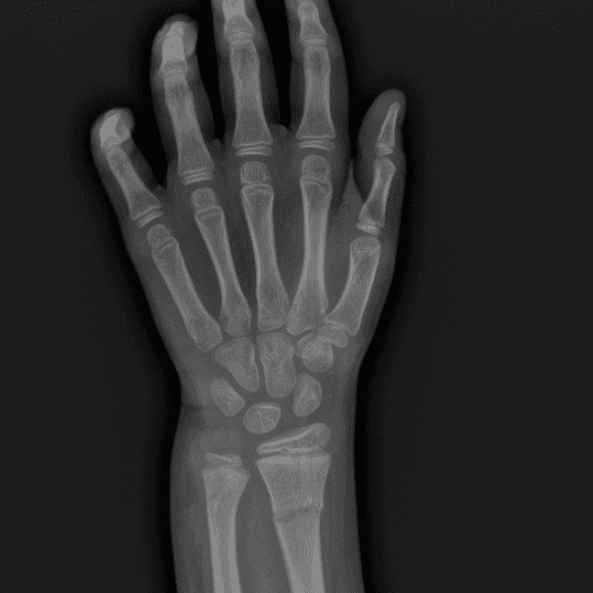

Simulates call by including subtle or difficult cases and some normals.

30 cases